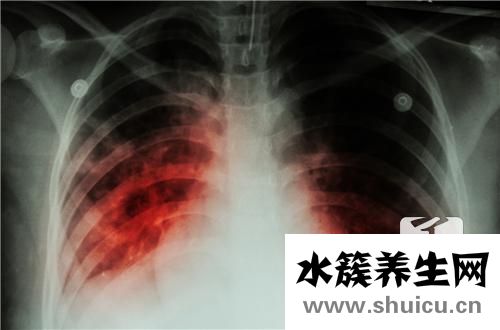

肺結核病是由結核病分枝桿菌感染肺臟造成的漫性傳染性疾病。是各種各樣結核病中最普遍者。我國完全免費醫治肺結核應該是永久性的,但我國完全免費醫治肺結核并不是永久免費的:

肺結核這類疾病的發展趨勢有一個全過程。剛開始的時候,病情一般不容易嚴重,最常見的是發熱咳嗽。這種病常被誤診為普通發熱感冒,很容易錯過肺結核。所以要學好,要清楚。...

肺結核的巨大不良影響大家都知道,甚至可能嚴重危及患者的人身安全。但如果肺結核能及時治療,患者立即到正規醫院治療,就能徹底治愈,不會造成很大危害。因此,結核病篩查是一項非常關鍵的任務。結核病篩...